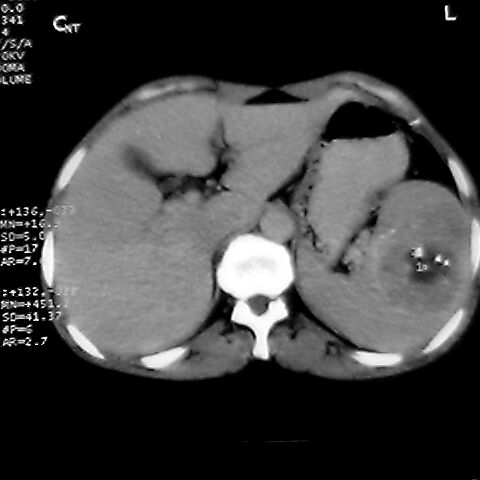

女 48岁 食道癌术前体检发现脾占位。

脾胀内部巨大低密度肿块,边界清或不清,中心坏死,轻度增强,内见散在钙化,结合食道癌病史多考虑:转移癌.

1肝右下叶小囊肿2右肾上极囊肿或错构瘤3脾脏不典型血管瘤可能性大.

脾脏低密度灶伴钙化,增强化明显,中心见液化坏死灶,强化延时明显。考虑血管瘤。转移瘤待排。

右肾见类圆形低密度影.结合病史.脾及右肾转移性ca可能性大